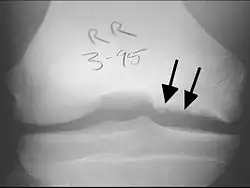

X-rays show lucency of the ossification on the anterior aspect of the knee in juvenile patients. In older people, the lesion typically appears as an area of osteosclerotic bone with a radiolucent line between the osteochondral defect and the epiphysis. The visibility of the lesion depends on its location and on the amount of knee flexion used. Harding described the lateral X-ray as a method to identify the site of an OCD lesion.[36]

To diagnose osteochondritis dissecans, an X-ray, CT scan or MRI scan can be performed to show necrosis of subchondral bone, formation of loose fragments, or both.[30] Occasionally a nuclear medicine bone scan is used to assess the degree of loosening within the joint.[31]